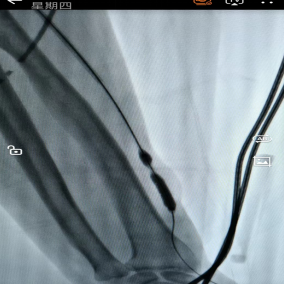

痛风是一种常见的代谢性疾病,当人体尿酸生成过多或排泄不畅,导致血液中尿酸水平升高(男性高于420μmol/L,女性高于360μmol/L),就可能形成尿酸盐结晶沉积在关节等处,引发剧烈疼痛(急性痛风性关节炎)、痛风石,甚至可能损害肾脏、引发心血管疾病等风险。 【尿酸失衡是罪魁祸首】 痛风的根源在于“尿酸代谢失衡”。人体嘌呤(来自食物和自身细胞)代谢后产生尿酸,通常由肾脏排出维持平衡。失衡后,未排出的尿酸会形成尿酸盐结晶沉积于关节、肾脏等部位,引发炎症和损伤。 高嘌呤饮食(如海鲜、动物内脏、浓汤)、饮酒(尤其啤酒)、剧烈运动、受凉、肥胖、熬夜、情绪压力等都可能是引起尿酸代谢失衡的诱因。 【管好生活方式,减少发作风险】 1.饮食上:减少高嘌呤食物摄入,可多选择蔬菜、水果、谷物、低脂奶制品等低嘌呤食物,严格控制酒精摄入,多喝水(心肾功能正常者每日 2000-3000ml),少喝含糖饮料。 2.体重管理:肥胖与痛风关联密切,通过合理饮食和适度运动逐步减重,避免过快减重。 3.运动和保暖:急性期需休息,缓解期选择游泳、散步、骑车等温和运动,减少关节冲击,并注意关节保暖,避免受凉。 【规范治疗:止痛与降尿酸并重】 ✓急性发作期:此时需要快速消炎止痛,常用药物包括非甾体抗炎药(谨遵医嘱,注意胃肠反应)、小剂量秋水仙碱、或短期糖皮质激素。请注意:急性期通常不自行加用降尿酸药。 ✓缓解期管理:长期规律降尿酸是减少复发的核心,药物需在医生指导下选择(如别嘌醇、非布司他抑制生成;苯溴马隆促进排泄,注意多饮水碱化尿液),将血尿酸持续控制在合适水平(如无痛风石者<360μmol/L,有痛风石者<300μmol/L)。切记:即使无症状,也需遵医嘱坚持服药。 【定期监测与长期坚持】 定期关注尿酸指标,初始治疗每2-4 周一次,稳定后每3个月一次,达标后每半年一次。每年筛查肾功能、尿常规等,记录发作情况,便于调整治疗方案。 【重要提醒】 痛风是可防可控的慢性病,别信偏方!通过科学的生活方式调整、规范的药物治疗和规律的监测随访,就能有效减少发作频率,保护关节和肾脏功能。 注:部分图片来源于网络,如有侵权,请联系删除。 贵州航天医院肾脏风湿科专家简介 冯远军 中共党员,肾脏风湿、肝胆外科党支部书记,肾脏风湿科主任,主任医师 临床擅长:对慢性肾脏病、急性肾损伤、急慢性肾小球肾炎、肾病综合症、风湿性疾病、间质性肾炎、肾小管损伤等疾病的诊治及血液透析技术、动静脉内瘘成形术及疑难病例的诊治具有丰富的临床经验。 曾在上海市第一人民医院及贵阳市第一人民医院进修学习,贵州省医学会肾脏病学分会第五届委员会委员,遵义市医学会肾脏病学分会第一届委员会副主任委员,遵义市医学会风湿病学分会第一届委员会副主任委员,荣获“贵州航天劳动模范、遵义市汇川区先进工作者”,遵义市医疗事故鉴定专家库成员,主持省市级科研项目4项,完成4项,近5年发表论文10余篇,北大核心期刊1篇。 王卫华 肾脏风湿科主任医师 临床擅长:从事临床工作28年,擅长尿毒症患者血管通路的建设及维护(如标准和高位动静脉内瘘术、取栓+内瘘重建术、内瘘狭窄球囊扩张术、长期中心静脉置管术及肾穿刺活检术)等手术,对原发性和继发性肾病综合征、急、慢性肾小球肾炎、慢性肾脏病、泌尿系感染、结缔组织病、急性中毒、痛风、贫血、血小板减少症等疾病诊治及血液透析技术应用等具有丰富的临床经验。 1995年毕业于遵义医学院临床医学系,曾前往重庆医科大学进修学习肾脏疾病及血液净化;遵义市医学会肾脏病学分会常务委员,遵义市血液净化质量控制中心委员;先后发表肾病专业省部级医学刊物医学论文8篇,主持市级科研项目2项。 李丽华 中共党员,肾脏风湿科副主任医师 临床擅长:从事临床工作17年,对慢性肾脏病、急性肾损伤、急慢性肾小球肾炎、肾病综合征、风湿性疾病、间质性肾炎、肾小管损伤、急慢性肾衰竭的血液透析、CRRT治疗以及血管通路的建设维护等具有丰富的临床诊疗经验。 2006年毕业于遵义医学院临床专业,曾在遵义医学院附属医院完成住院医生规范化培养,并前往第三军医大学新桥医院、珠海市人民医院进修学习;中华医学会遵义市肾脏病学分会委员,遵义中医药学会肾病专业委员会委员,遵义市血液净化质量控制中心委员,遵义市医学会血液学分会委员会委员;发表省部级医学刊物医学论文4篇,主持参与省级科研课题1项,主持参与市级科研课题1项,院级新技术6项,获得本专业授权实用新型专利3项。 李 玫 中共党员,肾脏风湿科副主任医师 临床擅长:从事临床工作15年,对慢性肾脏病、急性肾损伤、急慢性肾小球肾炎、肾病综合征、风湿性疾病、间质性肾炎、肾小管损伤等疾病的诊治具有丰富的临床经验,擅长血液透析技术、动静脉内瘘成形术等。 2008年毕业于遵义医学院临床医学系,曾前往遵义医学院附属医院进修学习肾脏病与血液净化相关技术;遵义市医学会肾脏病学分会委员,发表肾病专业省部级医学刊物医学论文4篇。 贵州航天医院肾脏风湿科简介 基本情况 贵州航天医院肾脏风湿科2017年建立,住院患者承载能力达到50人左右,透析治疗服务惠及250余人的患者群体,在学科建设、高端医疗设备引进及专业技术队伍已达到区域内领先水平。科室共有医护人员46名,副高级以上专家7名,亚专业设置齐全,涵盖肾脏疾病、风湿免疫疾病药物治疗、透析治疗及透析通路维护等多个专业领域,为患者提供全面、精准、高效的诊疗服务。配备了尖端的医疗设备与智能化的辅助系统,包括透析机、CRRT机等设备。 专科特色 (一)肾脏病治疗领域:专精于血液透析、血液透析滤过、血液灌流、血浆置换、CRRT等尖端技术,致力于为患者量身打造个性化的肾脏替代治疗方案。 (二)在风湿病治疗方面:凭借生物制剂、免疫抑制剂等前沿药物,结合患者的具体情况,精心策划个体化的治疗策略,有效减轻患者症状,显著提升生活质量。 超声引导下球囊扩张术:内瘘狭窄是内瘘最常见的并发症之一,我们采用先进的超声引导下球囊扩张术,通过微创方式恢复内瘘通畅,有效避免了传统手术带来的创伤和痛苦。 内瘘血栓溶栓治疗、取栓术:血栓形成是内瘘功能丧失的主要原因之一,根据患者具体情况,采用溶栓治疗、取栓术等多种手段,确保患者及时恢复透析治疗。 内瘘动脉瘤形成治疗:动脉瘤是由于内瘘局部血流动力学改变引起的血管扩张性疾病,采取佩戴弹力绷带、手术修复等措施,防止动脉瘤进一步发展和破裂。 内瘘感染治疗:内瘘感染是内瘘并发症中最为严重的类型之一,一般采用敏感抗生素进行抗感染治疗,严重者采取手术清创等措施。 内瘘窃血综合征治疗:是由于内瘘建立后,远端肢体血流减少引起的一系列症状,通过调整透析方案、改善内瘘血流分布及必要时重建内瘘等措施,有效缓解患者的症状并提高其生活质量。 诊疗范围 擅长治疗急慢性肾炎、肾病综合征、肾衰竭等肾脏疾病;擅长治疗类风湿关节炎、系统性红斑狼疮、干燥综合征等风湿免疫性疾病,并为患者提供健康教育与康复指导,帮助患者更好地管理疾病,提高生活质量。 END